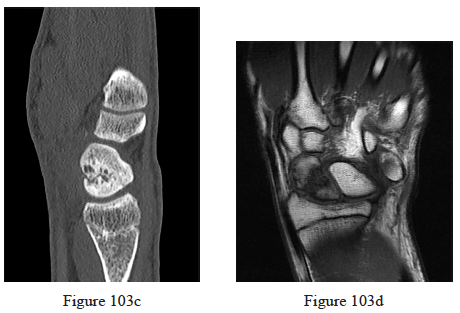

103. Figures 103a through 103d are the radiographs, sagittal-cut CT scan, and coronal T1 MR image of a 16-year-old boy who has wrist stiffness and pain after sustaining an injury 2 years ago. There is no bleeding from the proximal pole during surgery. Which procedure will most likely result in restoration of alignment and healing?

Moon ES, Dy CJ, Derman P, Vance MC, Carlson MG. Management of nonunion following surgical management of scaphoid fractures: current concepts. J Am Acad Orthop Surg. 2013 Sep;21(9):548-57. doi: 10.5435/JAAOS-21-09-548. Review. PubMed PMID: 23996986.

Jones DB Jr, Bürger H, Bishop AT, Shin AY. Treatment of scaphoid waist nonunions with an avascular proximal pole and carpal collapse. A comparison of two vascularized bone grafts. J Bone Joint Surg Am. 2008 Dec;90(12):2616-25. doi: 10.2106/JBJS.G.01503. PubMed PMID: 19047706.